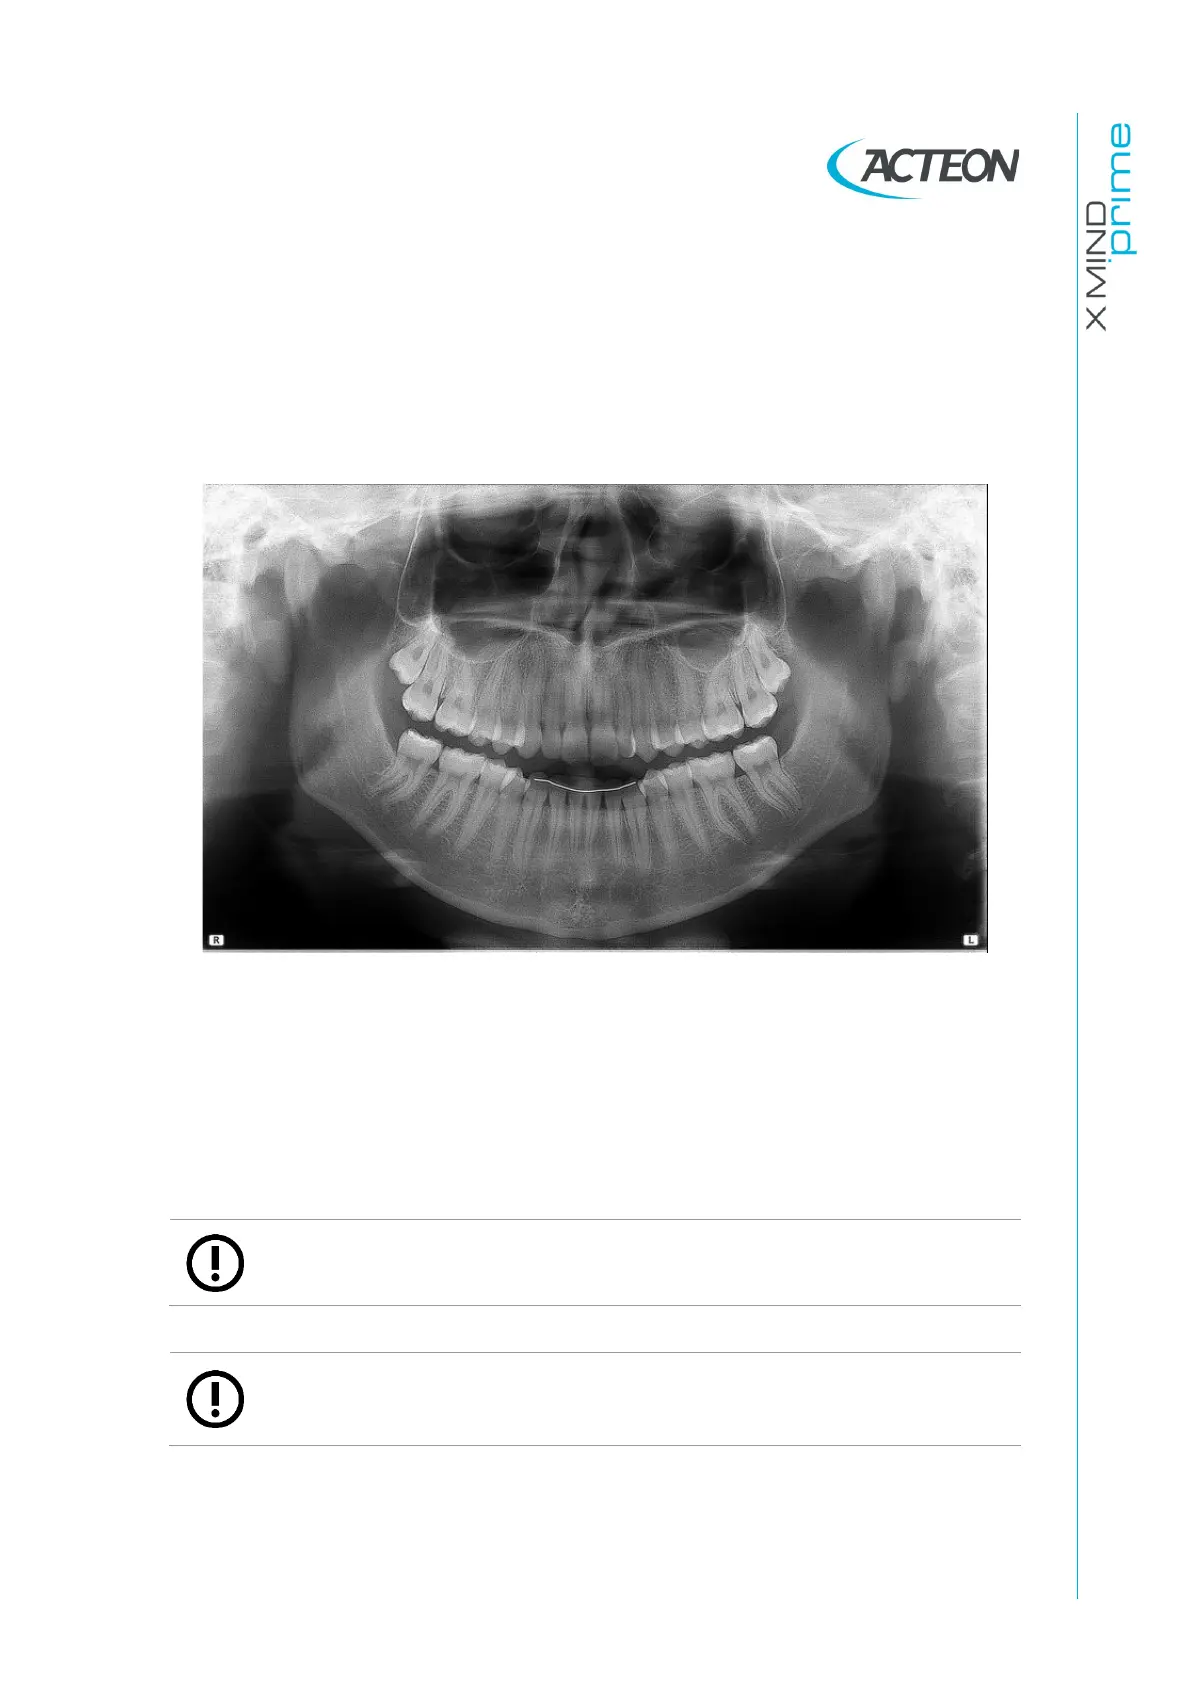

The result of all the above listed actions will be a radiography where all the parts are

properly exposed and are well identifiable as shown in Figure 33.

Figure 33

In a good panoramic image, all anatomic structures are well represented and an equal

magnification and sharpness of all structures can be seen.

The image must be symmetric, with the ascending rami of the temporo mandibular joints

almost parallel and showing posterior vertical borders. The occlusal plane is quite

smiling, despite this the palatal plane does not overlap the apex of the upper arch and

therefore allows a good view of the apex itself. The spine is well compensated.